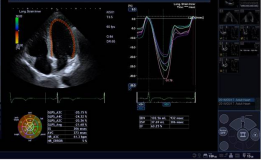

1) 二维/三维室壁运动追踪技术 (2D/3D Wall Motion Tracking)